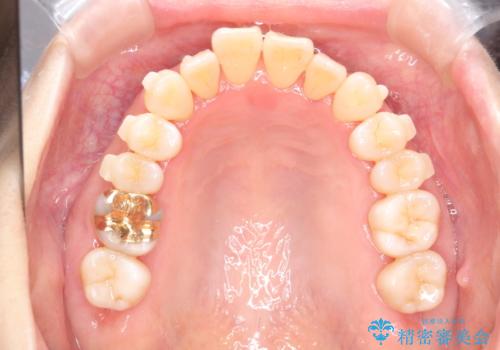

マウスピース枚数 初回36枚 + 追加26枚

概ね1年4ヶ月で治療完了しました。

マウスピース矯正は開咬(オープンバイト)に対して有利な治療メカニクスを持ちます。

当院独自の工夫を随所に盛り込み、狙い通りの治療結果が得られました。